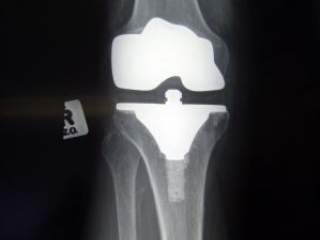

Naše zglobove od povrede štite ligamenti, mišići i tetive. Jaki mišići i snažne tetive i još snažniji ligamenti će sprečiti da se desi trauma zgloba. Traumatske povrede samih zglobova su retke, jer je potrebno delovanje velike sile da bi to takve povrede došlo.

Naši zglobovi su većinom kuglasti zglobovi, tj. omogućavaju pokretanje koštanih poluga u pravcu fleksije i ekstenzije, abdukcije i addukcije i rotacije. Ove pokrete kontrolišu i regulišu i zglobna kapsula, zglobne veze, ligamenti i same anatomske barijere.

Ukoliko u porodici imamo nekoga ko pati od artritisa onda znamo da treba da preduzmemo par mera kako bismo sprečili da naši zglobovi obole od ove hronične bolesti. Treba pokušati smanjiti prekomernu telesnu težinu, jer zglobovi moraju nositi svaki dodatni kilogram.